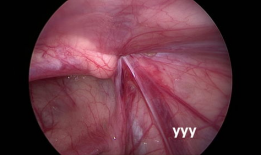

疝气手术视频,从术前准备到术后恢复

你有没有想过,当你在网上搜索“疝气手术视频”时,会出现什么样的画面呢?今天,就让我带你一起揭开这个神秘的面纱,看看那些让人既好奇...

2025-08-25 134 -